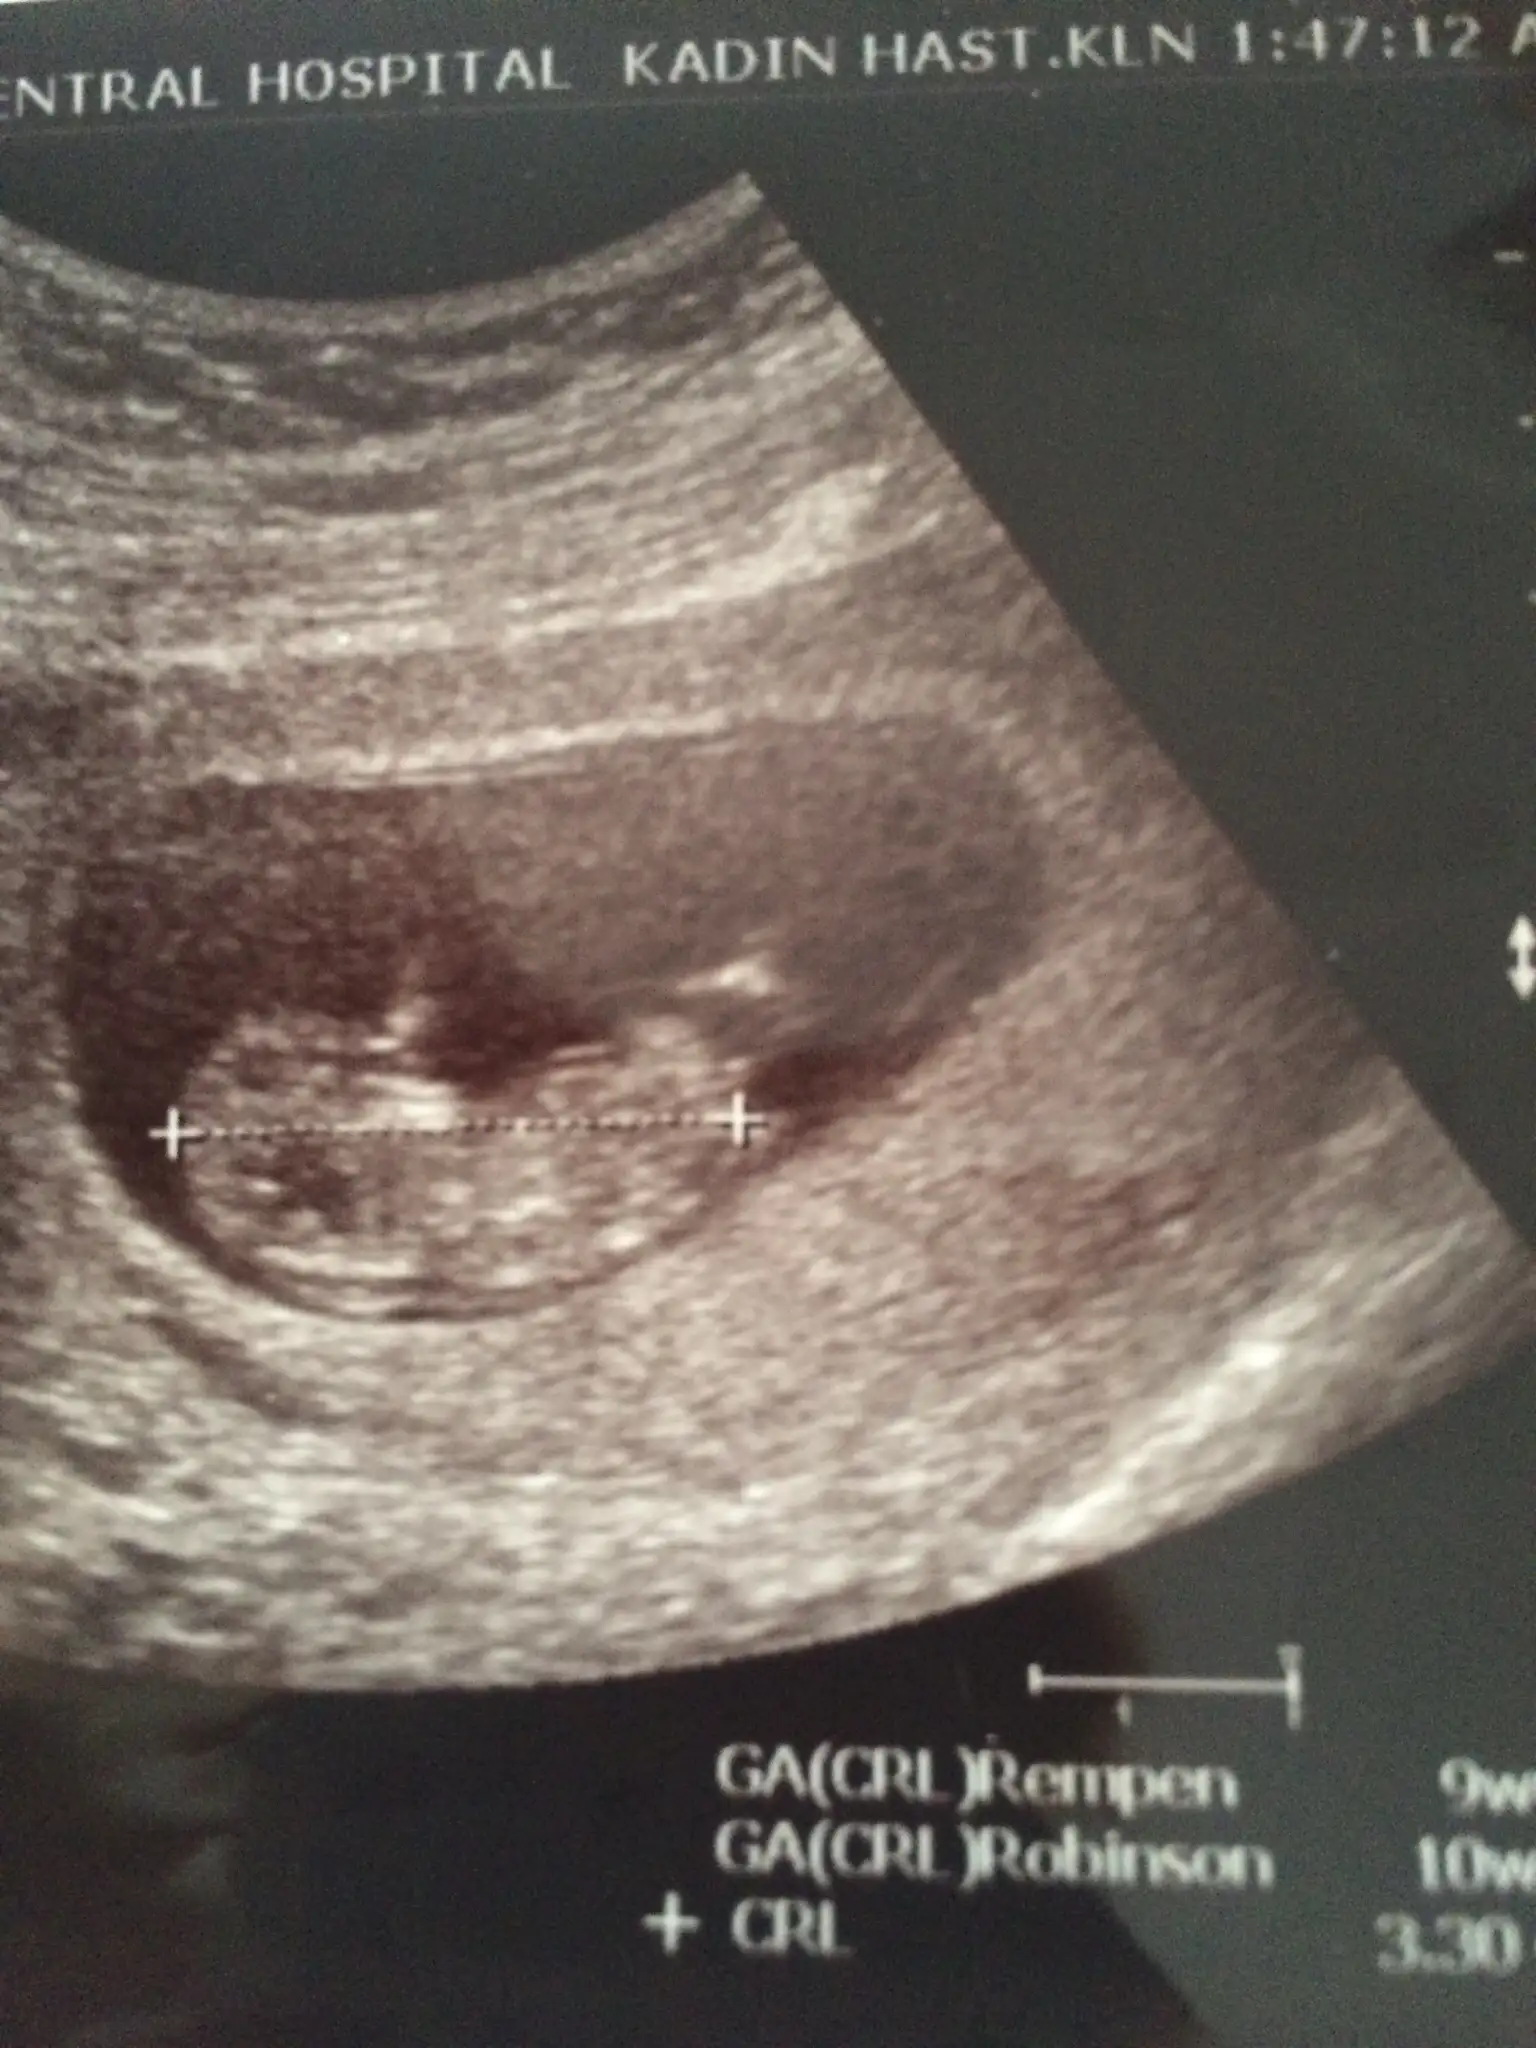

hoşbuldum canım 8+5 te gittim dr a kalp atşını duydum şükür ama 5 günlük geç döllenme var dedi dr :/ tam 8 haftalık dedi bakalım

Kızlar usg leri nasıl ekleyebiliriz buraya bulamadım